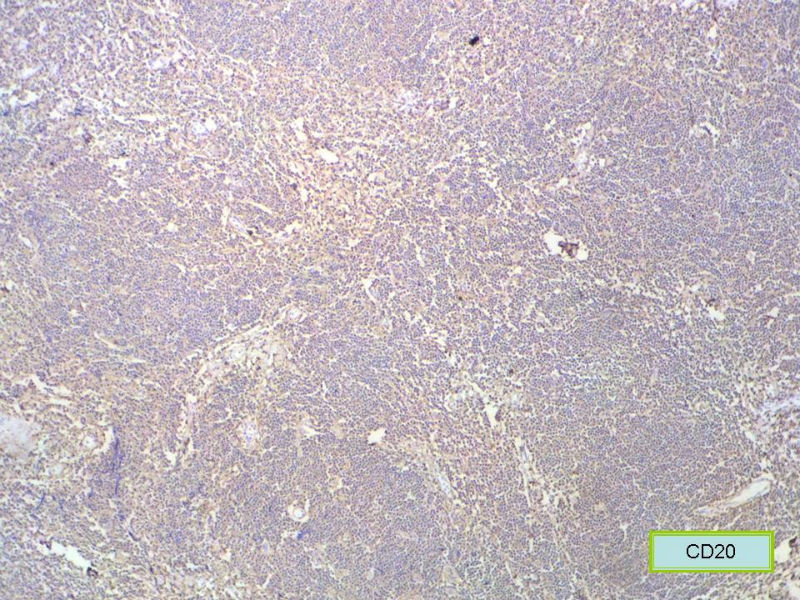

请再标记CD20和CD79a!图片中阳性不明确,根据T细胞标记看,应该是B细胞结节。Ki67散而少,不支持低级别滤泡性淋巴瘤,若B细胞弥漫阳性,则是惰性B细胞非霍奇金淋巴瘤,首先考虑套细胞,然后是边缘区淋巴瘤。不做生发中心标记,Bcl-2在小B细胞淋巴瘤分类中无意义。

赞成以上专家的讨论,根绝病史,HE形态考虑小细胞病变,CD3、CD5散在+,还是倾向淋巴造血系统病变,CD20、CD79a阳性不明确,可以考虑复查,加做PAX-5,核阳性容易判断,另再加做鉴别其它小细胞肿瘤的抗体:CD99、CD43、CyclinD1、CK、CgA、Syn等,了解病史:骨髓、末梢血、肝、脾等。

CD20(+),Kappa(+),ki-67(+)>2%,Lambda(+),Pax-5(+),符合粘膜相关淋巴瘤。

本例是发生在特殊部位“结膜下”,HE肿瘤细胞形态形态一致,形似单核样B细胞。B细胞标记若明确阳性,诊断MALT是挺合理的。